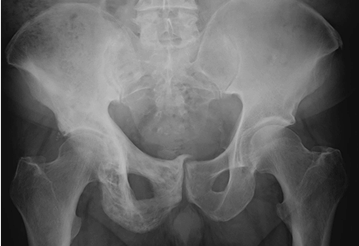

Fig 50. Enfermedad de Paget en fase esclerótica.

Rx AP. Zona esclerótica con engrosamiento del hueso, que compromete el techo del acetábulo, los ramos ilio e isquiopúbico en el lado derecho.